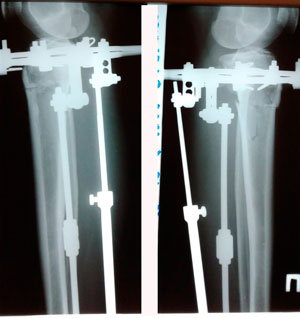

Рентген на фиксации

Вложения